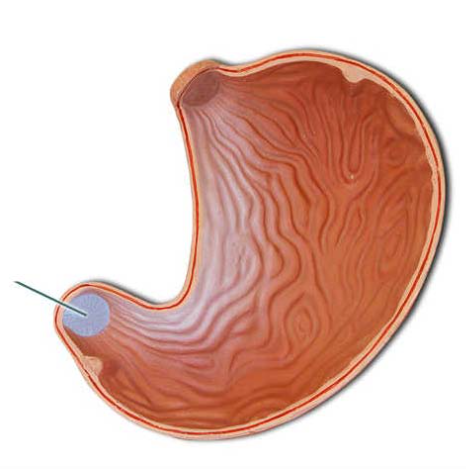

Identify the highlighted structures.

rugae